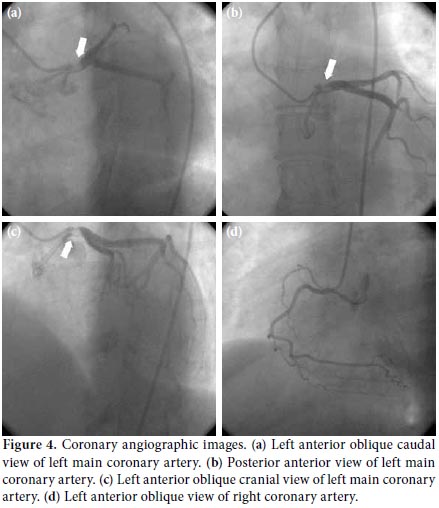

A 48-year-old female patient with no known cardiovascular risk factors was referred to our emergency department due to the sudden onset of severe, constricting chest pain that had been occurring for the previous four hours. On physical examination, blood pressure measurements from the right and left arms were 155/90 and 130/80 mmHg, respectively, and an apical 2/6 systolic heart murmur was heard. Electrocardiography (ECG) showed a 1 mm ST-segment depression in the precordial derivation and a 1.5 mm ST elevation in augmented vector right (aVR) (Figure 1). Laboratory tests revealed a creatinine level of 1.8 mg/dL, a urea level of 80 mg/dL, and slightly increased troponin/creatine kinase-MB fraction (CKMB) levels. Based on the patient's medical history, she had been diagnosed with Takayasu's arteritis 12 years earlier due to renal artery stenosis, subclavian artery stenosis, and intermittent claudication. In addition, a pulmonary embolism had been detected four years previously. Transthoracic echocardiography showed normal left ventricular systolic function, mild aortic regurgitation, and moderate tricuspid regurgitation. The systolic pulmonary artery pressure was 35 mmHg. The ascending aorta was measured as 4.0 cm, and no dissection flap was detected. An echocardiographic examination revealed that the proximal aorta was thickened and hyperechogenic, and calcific plaques were commonly observed on the inner surface of the lumen (Figure 2). Using suprasternal imaging, it was determined that the arcus aorta was 4.3 cm in width, and moderate proximal brachiocephalic, common carotid, and subclavian artery stenoses were detected. Thickening of the arcus aorta wall was observed in addition to an increased echogenic area and a rough inner lumen (Figure 3). Due to ongoing severe chest pain, the patient was urgently transferred to the catheter laboratory. Spontaneous dissection causing severe stenosis in the proximal left main coronary artery (LMCA) was detected by coronary angiography (Figure 4), but all other coronary vessels were normal. In addition, there was no significant narrowing observed on the carotid Doppler ultrasound. The patient's hemodynamic values were normal, and an emergency operation was planned. Ascending aorta, upper, and lower vena cava cannulations were performed after a median sternotomy and then the patient entered into the pump. The heart was stopped by cold potassium while the patient was under general (rectal temperature 28 °C) and topical hypothermia. During an intraoperative evaluation of the thoracic aorta, it was noted that it was completely calcified and hardened. Aortocoronary anastomosis was performed using a saphenous venous graft because of the ostial involvement of the subclavian and left internal mammary arteries (LIMA). The postoperative course was uneventful, and the patient was discharged on postoperative day 10.

Takayasu's arteritis, also known as Martorell's syndrome, is an inflammatory disease that often affects the aorta and the proximal segments of the main aortic. It also may result in vascular occlusion due to intimal fibrosis and thickening. In addition to ostial stenosis, aorta aneurysms may be encountered, depending on the existence panarteritis. This is especially true if there is destruction of the tunica media. The cause of Takayasu's arteritis is not yet known, but it is more common in young females. Symptoms vary depending on the involvement and severity of the functional impairment of the organs supplied by the stenotic vessels. During the early stage, rheumatic complaints such as fever, malaise, fatigue, general body pain, and weight loss may occur due to the systemic inflammatory condition. As a result of chronic vascular inflammation, intimal fibrosis may result in catastrophic outcomes, such as organ ischemia. Arm and leg pain, renovascular hypertension, and neurological symptoms may develop in patients during advanced stages of this disease. Pulmonary arterial hypertension and emboli are also often observed due to the involvement of the pulmonary artery. A diagnosis of Takayasu's arteritis is made clinically according to the presence of at least three of the American College of Rheumatology (ACR) 1990 criteria:[2] (i) disease onset prior to age 40, (ii) claudication of the extremities, (iii) reduction in the brachial pulse, (iv) more than a 10 mmHg pressure difference between the two arms, (v) detection of a murmur around the aorta, subclavian artery, or both, and (vi) abnormal arterial imaging. There are no specific blood tests for Takayasu's arteritis. Medical treatments include immunosuppressive therapy, such as steroids, cyclophosphamide, and methotrexate, but there is no current agreement on the best treatment option. Coronary artery involvement occurs in 5-15% of patients. Although Takayasu's arteritis often causes ostial stenosis, spontaneous LMCA dissection is an extremely rare complication.[3] In the case of sudden-onset chest pain in a patient with this disease, coronary artery dissection should be considered due to the need for early diagnosis and rapid treatment. However, dissection of the ascending aorta should be excluded. In our patient, transthoracic echocardiography (suprasternal view) did not show aortic dissection. Therefore, computed tomography (CT) and magnetic resonance imaging (MRI) were not performed because of poor renal function. An echocardiographic examination should be used during routine follow-up of all patients with Takayasu's arteritis to evaluate aortic involvement. Transthoracic echocardiography is non-invasive and inexpensive and has been proven to be an excellent method for patient diagnosis and follow-up. Intimal thickening and hyperechogenic appearance due to calcification of the aorta and its major branches are important and valuable observations. As in our patient, echocardiography may be useful as an alternative to MRI and CT for detecting ostial stenosis of the main branches. Percutaneous coronary intervention (PCI) for left main coronary stenosis has been described in the literature; however, invasive treatments should be decided upon according to the lesion location, number of stenotic vessels, and available technical equipment.[4] There are currently no clinical studies showing the superiority of percutaneous intervention over surgical therapy in patients with Takayasu's arteritis complicated by left main coronary dissection. Due to the risk of entering a false lumen, surgical management was planned. In our patient, an internal mammary artery (IMA) graft was not used because there were advanced fibrotic changes and calcification in the aorta and its major branches. A saphenous graft was preferred, as previous reports have shown lesser venous involvement with this procedure.[5] A careful preoperative echocardiographic examination with suprasternal views is suggested, which can provide the surgeon with adequate information regarding graft choice. When intimal thickening is intense and subclavian ostial stenosis is detected, saphenous graft selection should be given priority. No guidelines are currently available regarding percutaneous intervention to protect the LMCA following surgery for its dissection in patients with Takayasuʹs arteritis.